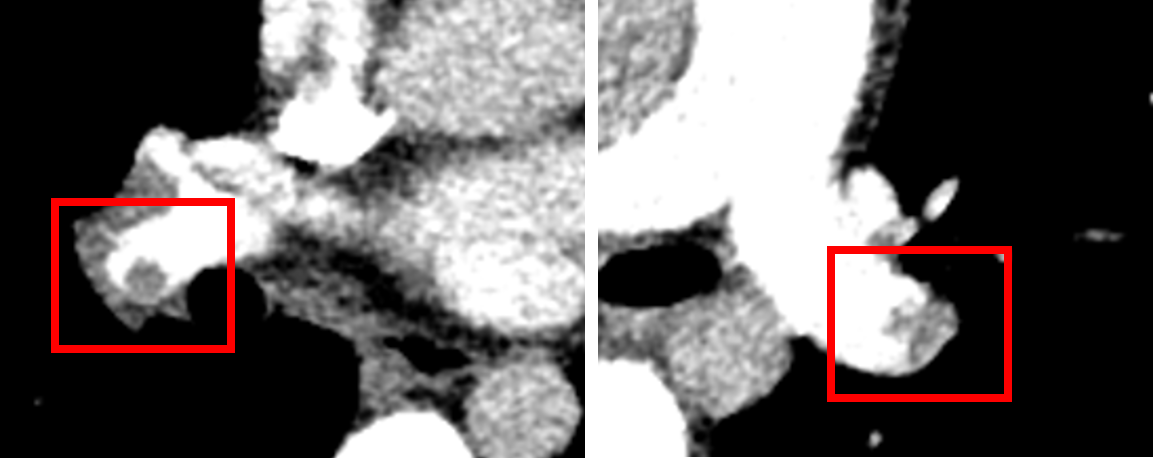

十七岁的小姑娘郑某这段时间总是无缘无故晕倒,起初家人以为是低血糖,给她吃点糖果也能好转。直至这种情况发生了好几次,同时小姑娘出现了明显的胸闷胸痛,家人才意识到不对,急急忙忙至苏州大学附属独墅湖医院呼吸与危重症医学科就诊。门诊医生立即为小姑娘完善了头颅、心超及相关的血检指标,结果提示小姑娘的血栓指标(D-二聚体)是正常值的数十倍,肺动脉的压力也明显升高。这让有经验的医生立即意识到不对,这个小姑娘可能患了一种致死率极高的疾病!于是立即将她收住入院,并完善肺动脉CTA检查,果然发现患者左右肺动脉主干及其主要分支可见多发的充盈缺损,最终确诊为肺栓塞,同时属于高危组。

住院期间我们密切监测患者血压、心率、脉氧及血栓、心脏相关指标,关注这些指标的变化以便及时调整患者治疗方案。万幸的是,患者在我们的治疗下病情逐步好转,各项指标均趋于正常,复查肺动脉CTA血栓明显好转稳定,最终序贯至口服抗凝治疗后顺利出院,后续继续口服药物治疗。